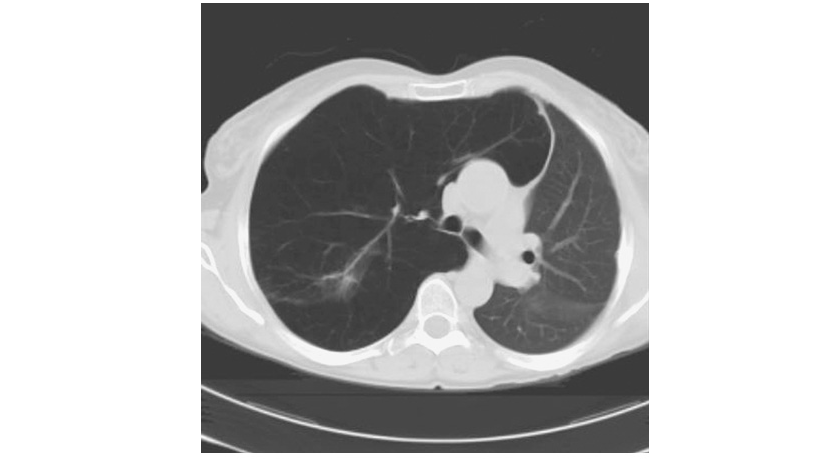

Radiographic studies may assist in the classification of the type of COPD. Obvious bullae, paucity of parenchymal markings, or hyperlucency suggests the presence of emphysema. Increased lung volumes and flattening of the diaphragm suggest hyperinflation but do not provide information about chronicity of the changes. Computed tomography (CT) scan is the current definitive test for establishing the presence or absence of emphysema in living subjects (Fig. G-4) and (Fig. G-5). From a practical perspective, the CT scan does little to influence therapy of COPD except in those individuals considering surgical therapy for their disease (described below).

severe upper lobe involvement in a 68-year-old man with a 70-pack-year smoking

history but forced expiratory volume in 1 s (FEV1) 81% predicted (GOLD

spirometry grade 1). B. Panlobular emphysema with diffuse loss of lung

parenchymal detail predominantly in the lower lobes in a 64-year-old man with

severe α1 antitrypsin (α1AT) deficiency. C. Paraseptal emphysema with marked

airway inflammation in a 52-year-old woman with a 37-pack-year smoking history

and FEV1 40% predicted.